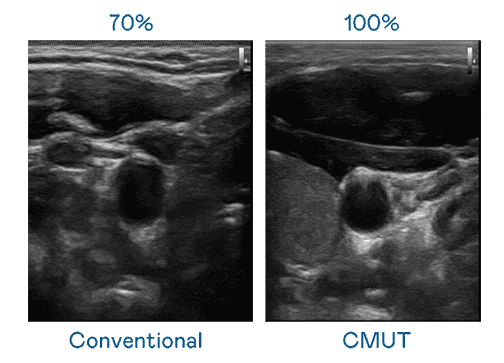

CMUT 技术是一种用电容式微机电元件来产生超音波讯号的技术。。与传统 PZT 压电式技术相比,,,,CMUT 频宽增加 30%,,,,更宽频的超音波讯号让影像解析度大幅提升,,是实现高影像品质医疗超音波扫描、、促进精准医疗发展的关键技术。。

大频宽带来超清晰影像

超音波影像的解析度高低,,,首先取决于探头能发出的讯号频宽。。。尊龙集团 CMUT 可提供高清晰的超音波讯号,,提供高频宽、、高灵敏度、、影像纹理细节更高的超音波影像,,,协助医护人员缩短影像判读时间及利用精准的医疗影像进行诊断。。。